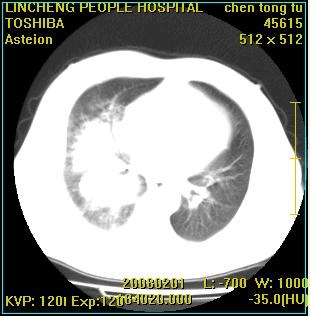

患者,男性,62岁。主因头晕,发热,咳嗽6天,高热达39度,esr19mm/h,wbc 3.9×10 9/l

实变区见空气支气管征,支气管通畅,考虑为大叶性肺炎,右侧少量胸水

实变区见空气支气管征,支气管通畅,考虑为大叶性肺炎,右侧少量胸水。